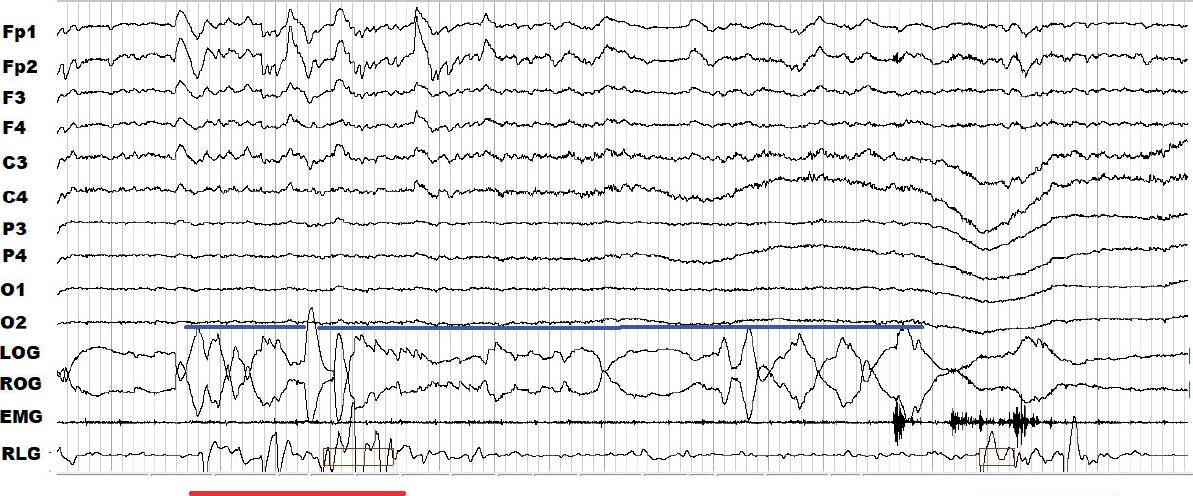

Tanto para el sueño NMOR como para el MOR hay dos posibles indicadores de la fragmentación: los movimientos periódicos de las piernas (MPP) y los arousals o alertamientos. Los MPP se observan en vigilia, el sueño NMOR y MOR, incluso cuando hay movimientos oculares rápidos. En esta última etapa de sueño MOR (Figura 6) se detectan proporcionalmente menos MPP que durante el sueño NMOR (Figura 7), debido a su atonía muscular característica (Rosales-Lagarde y col., 2009; Calvo y García-Borreguero, 2015). Los MPP y los alertamientos son fenómenos relacionados con las activaciones simpáticas del sistema nervioso y la frontera entre su caracterización como fenómenos normales o anormales continúa en debate (Ferri y Fulda, 2017; Parrino y Terzano, 2017). La frecuencia y las manifestaciones subjetivas de una mala calidad de sueño y/o la sensación de malestar en las piernas, son especialmente características del síndrome de piernas inquietas (SPI) (Ashbrook y During, 2017). El SPI implica el movimiento de las piernas involuntario con parestesias y dolor (Ashbrook y During, 2017).

Figura 6 Registro de la polisomnografía durante 30 s de la etapa de movimientos oculares rápidos (MOR) de una paciente con deterioro cognitivo leve. Se detectaron varios MOR (azul) en el canal correspondiente al electrooculograma. Los movimientos periódicos de las piernas (MPP) (rojo) coinciden con los MOR y los MPP se presentan en el canal correspondiente a RLG (right leg, por sus siglas en inglés).